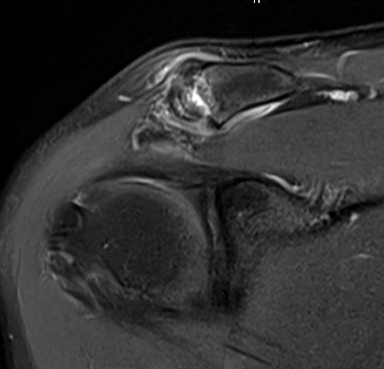

MRI

Acromioclavicular osteoarthritis

Grade I: Normal

Grade II: Capsular distension, bone marrow edema, mild joint narrowing

Grade III: Capsular distension, joint space narrowing, marginal osteophytes

Grade IV: Markedly abnormal ACJ with large osteophytes